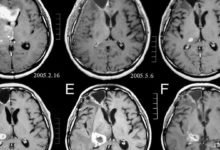

• Beyin Emarı (MR)